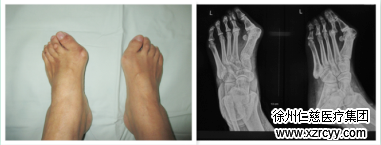

拇外翻畸形外观 拇外翻术前X线片

据了解,拇外翻又叫大脚拇,是由多种因素引起的第一跖骨向内位移,拇趾因肌肉牵拉而斜向外侧的畸形。从外形上看,是指脚拇趾向外倾斜超过十五度,拇趾内侧关节处肿大,偏向第二趾下,将第二趾抬高,第二趾足底下皮肤形成硬结,并且拇趾外翻同时也会伴有疼痛。

betway在线登陆手足显微外科专家曹广超主任介绍,拇趾外翻产生的主要原因主要有以下几种:一是来自家族遗传;二是穿夹脚鞋,一些头比较尖的皮鞋或者女士爱穿的高跟鞋引起的;第三个是有扁平足病的患者也容易拇趾外翻。

拇趾外翻这种病患者大部分是女性,特别是以中老年女性为主。尽管目前拇指外翻治疗已有很多种手术方法,但仍然没有一种方法可以解决所有问题。如何选择一种合适的方法来解决拇外翻是一般骨科医生感到困难的问题,betway在线登陆手足显微外科医生通过手术前认真检查,特殊X线拍片和足底应力分布测量,制定出最适合病人的手术方案——微创小切口拇外翻的截骨矫形术。